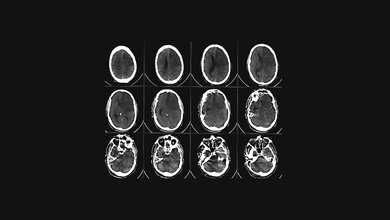

Probleme bei einem Schlaganfall

Wenn eine Verbindung aufgrund einer niedrigen Durchflussrate einmal sehr schwach geworden ist, kann dieser nur schwer wiederhergestellt werden. Ein häufiges Beispiel hierfür ist die Verstopfung eines Blutgefäßes, was im schlimmsten Fall sogar zu einem Schlaganfall führen kann. Bei einem Schlaganfall werden einige Blutgefäße in einer bestimmten Hirnregion durch die Verringerung des Blutflusses sehr schwach. „Wir haben festgestellt, dass in einem solchen Fall die Anpassungen im Netzwerk dauerhaft sind und auch nach der Beseitigung des Hindernisses beibehalten werden. Man kann sagen, das Netzwerk zieht es vor, den Fluss durch bestehende stärkere Verbindungen umzuleiten, anstatt schwächere Verbindungen neu zu bilden - selbst wenn der Fluss das Gegenteil erfordern würde“, erklärt Komal Bhattacharyya, Hauptautor der Studie.